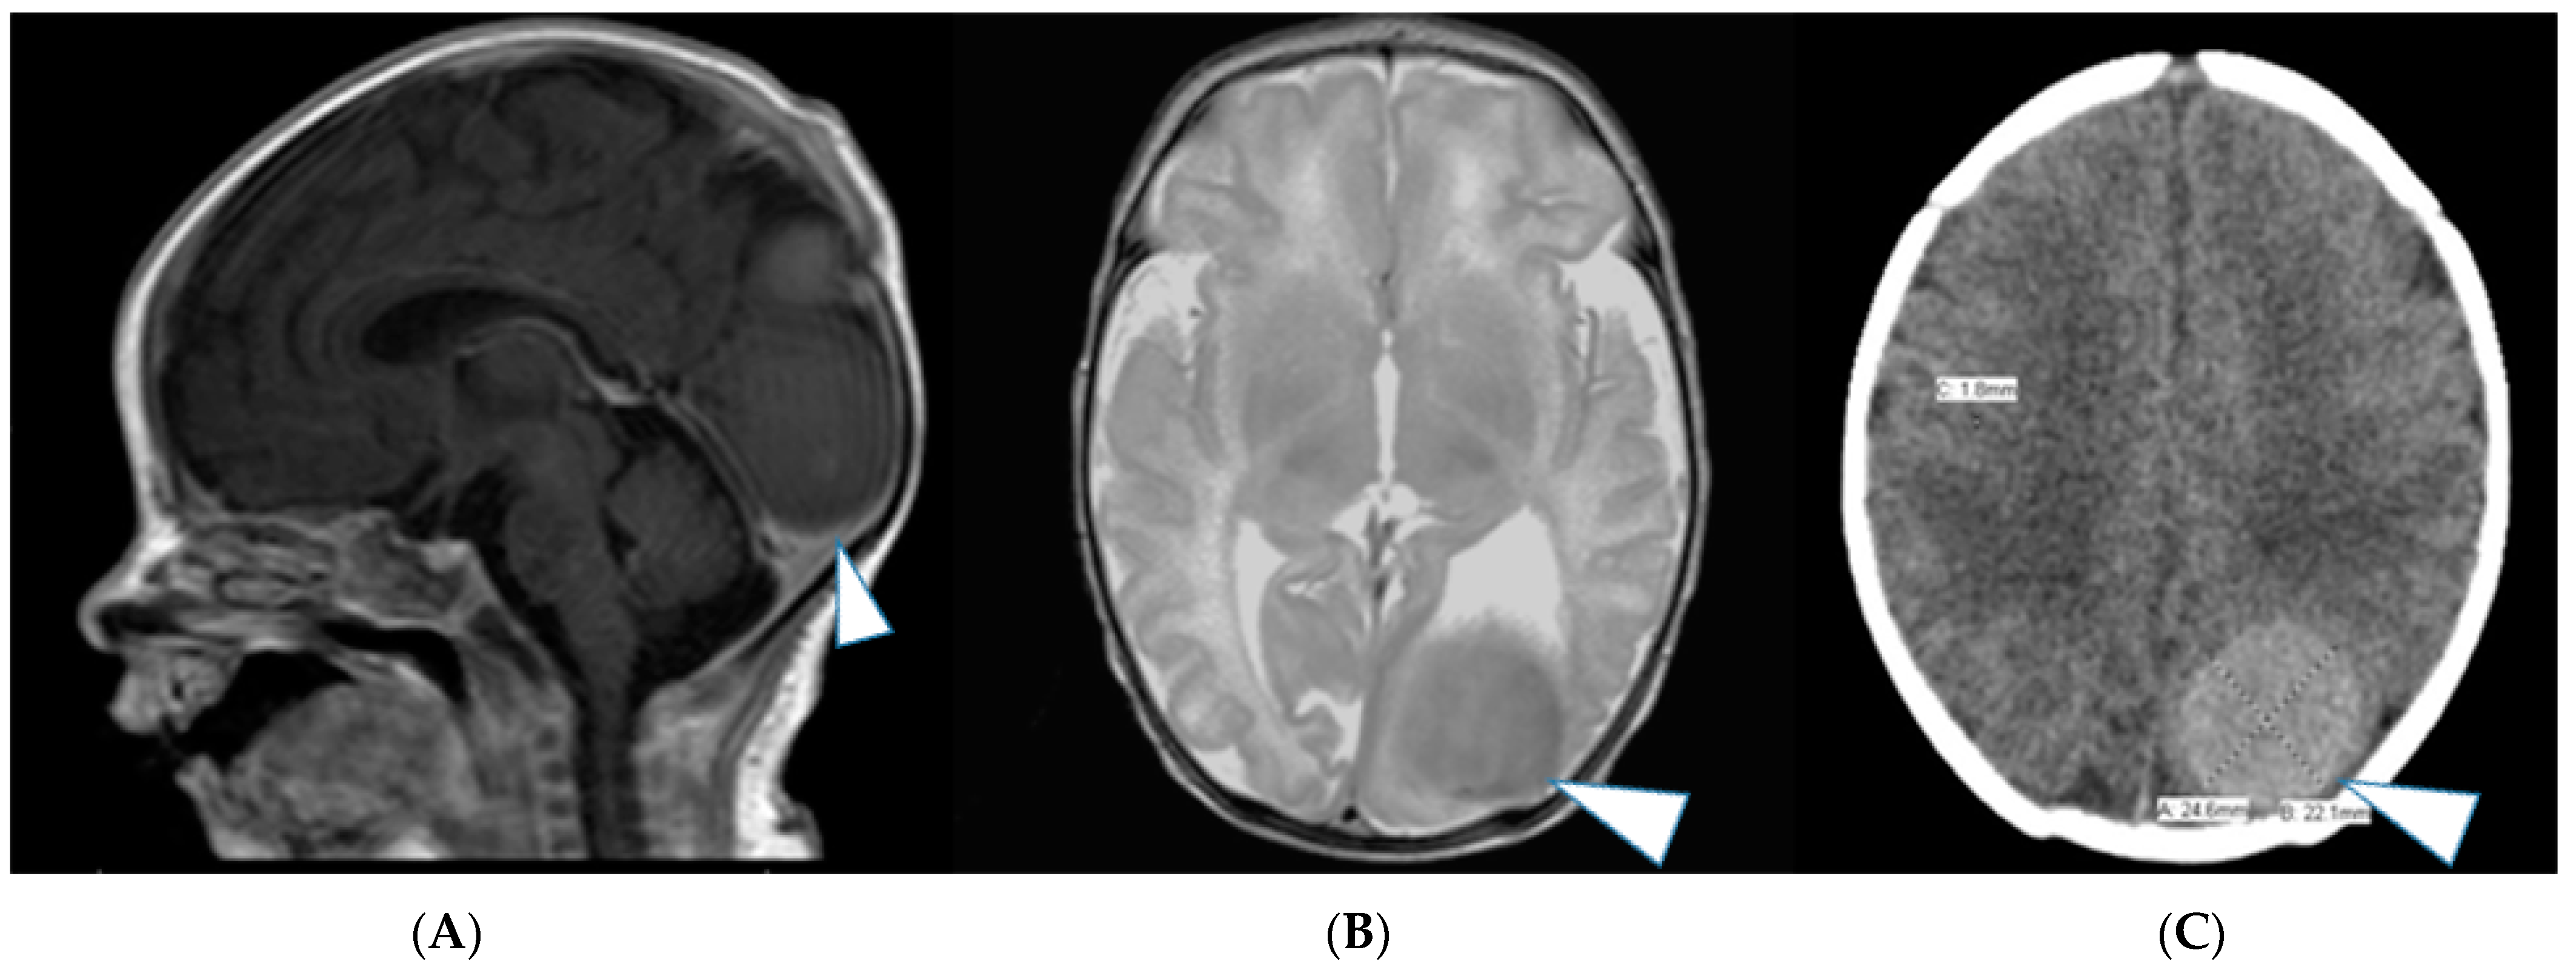

2. Case Series